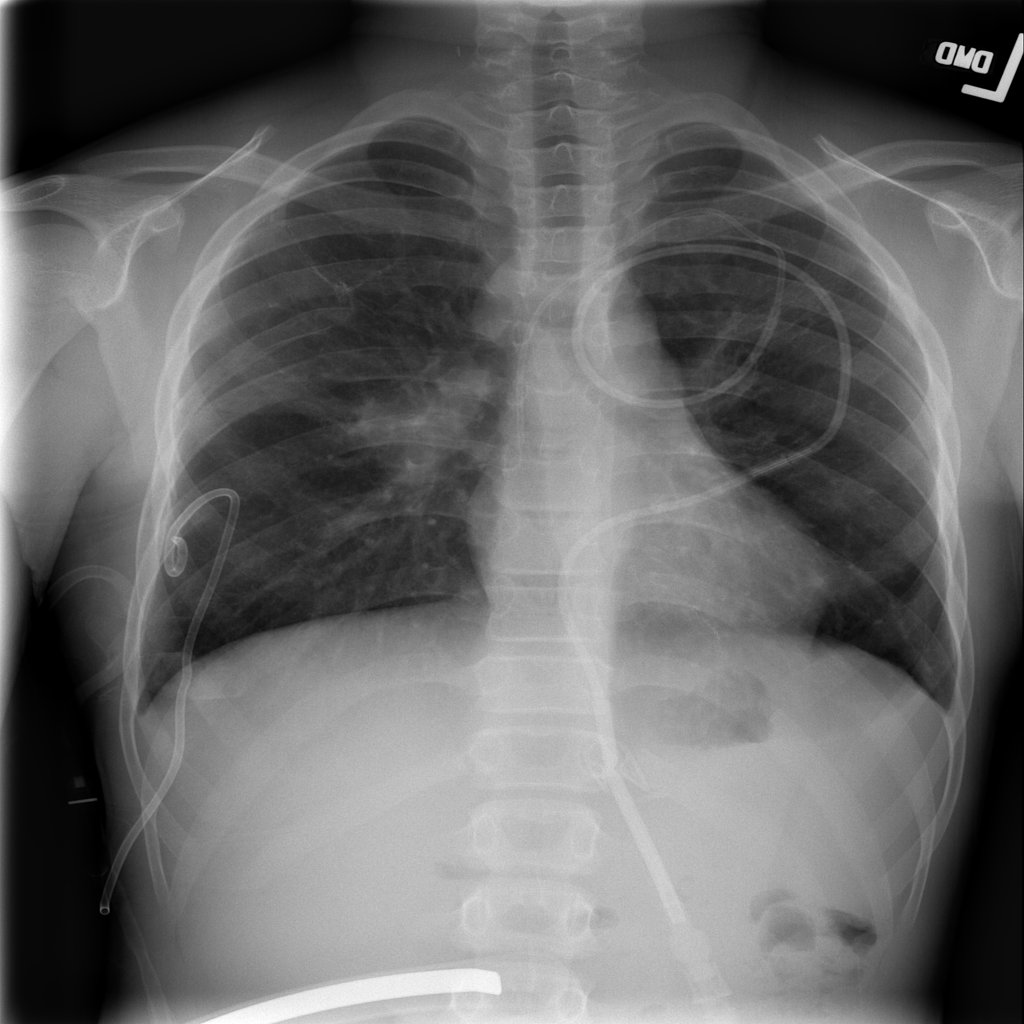

Mass

A mass is a larger focal opacity or lesion seen on the image. It is a descriptive finding that can have several causes and usually needs more imaging or clinical context to characterize.

PAT-4639 · IMG-024Mass

PAT-4639 · IMG-024

AP